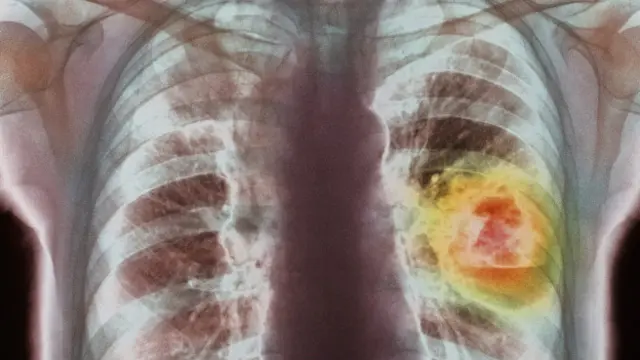

Tütün kullanımı, çoğu zaman ölümle sonuçlanan akciğer kanserinin yanı sıra, diğer pek çok hastalığın da en önemli nedeni.